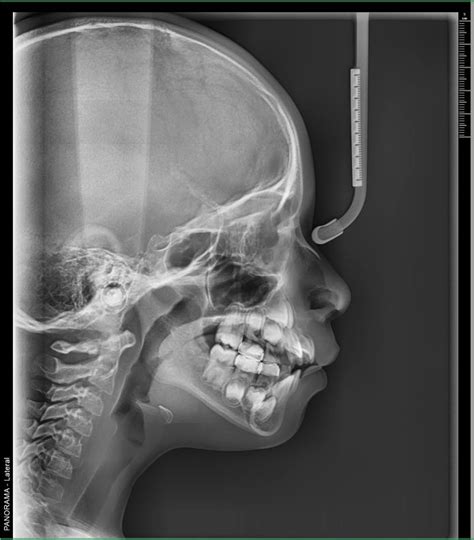

- Cefalometría o Telerradiografía: Prácticamente solo se usa para estudios previos a tratamientos de ortodoncia ya que permite analizar las relaciones entre diferentes estructuras óseas de la cara y cráneo y entre éstas y los dientes. Se utiliza principalmente en ortodoncia. Muestra la totalidad de la estructura facial y mandibular (arcadas superior e inferior, huesos maxilares, mandíbula y estructuras de soporte). Es un tipo de radiografía que, en el ámbito odontológico, prácticamente solo se usa en los estudios previos a una ortodoncia. Es fundamental para los análisis cefalométricos que determinan la posición y alineación de los dientes, así como la relación entre los maxilares y el cráneo.